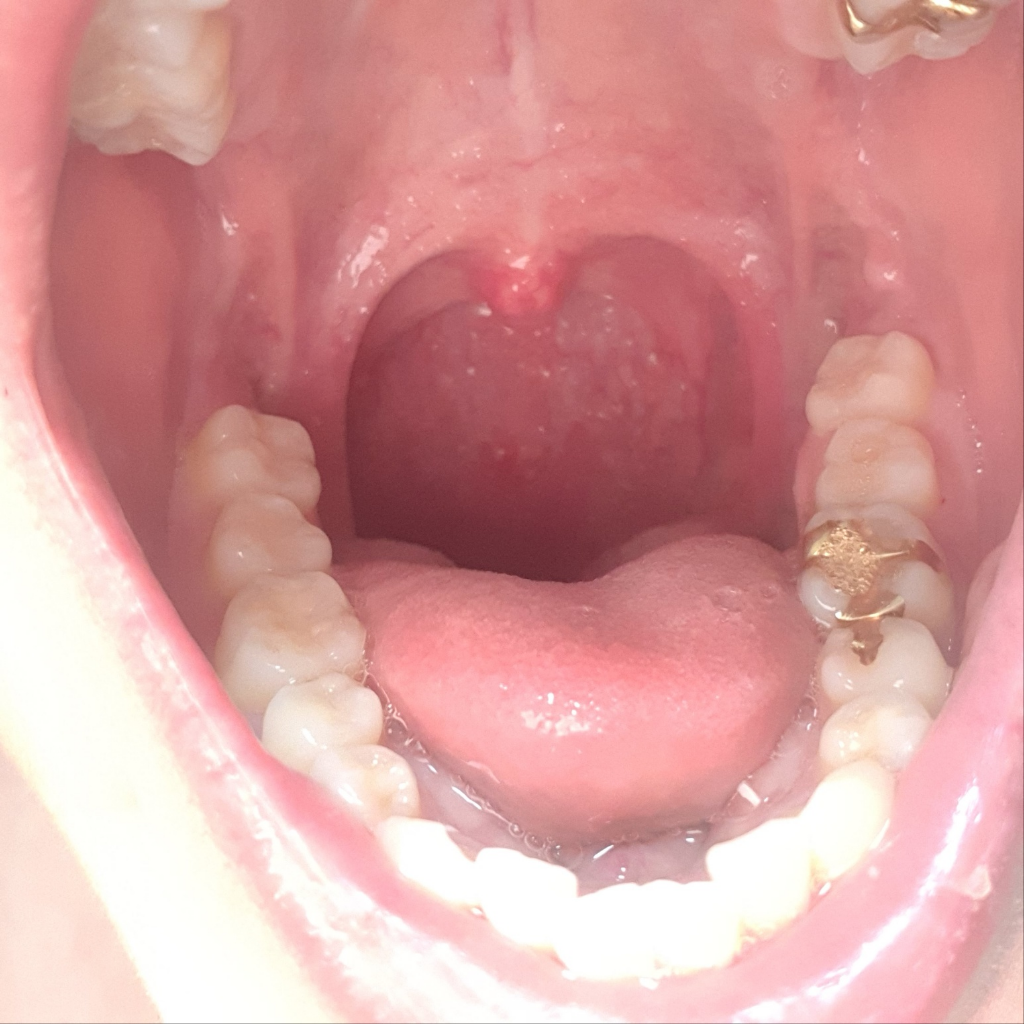

이정도면 편도가 큰건가요?제가 편도가 비대칭인데

편도가 제가 비대칭인데 한쪽이 약간 더 큰데 이비인후과에서는 아무소리도 없던데 요즘따라 더 커진 느낌인데 느낌상 이정도면 큰건가요??이거로 인해 불편한건 없습니다

• 1번 째 사진

• 사진의 소견만 놓고 정확하게 어떻다 말씀드리기는 부적절하긴 하나, 사진의 소견을 통해서 보았을 때에는 편도가 별로 크지 않습니다.

사진으로 볼 때 편도는 그리 큰 편이 아닙니다. 평균적인 수준이라고 볼 수 있겠고 걱정할만한 문제는 없어보입니다.